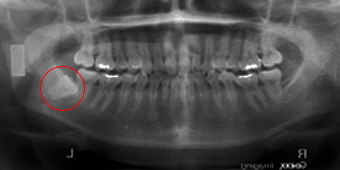

右側下顎水平智歯ですが写真拝見して頂きますと、手前の歯にめり込んで埋伏位置も深く2根に分かれてますので少し難しく10分程度かと思われます。